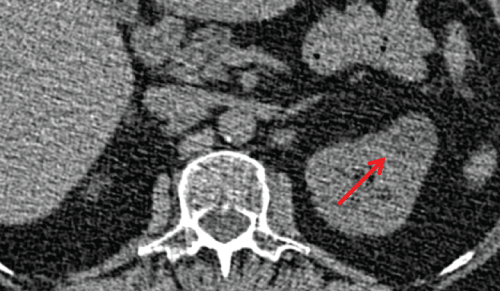

One hundred and thirty four (8.5%) exhibited findings of little or no clinical significance (category 1) for prevalence of 8.5 %. There was no change in size or attenuation of findings in any subject in category 1 on two subsequent annual screening CT scans. Incidental CT findings of variable clinical significance (category 2) were demonstrated in 44 out of 1572 subjects for prevalence rate of 2.8 %. One anterior mediastinal nodule increased in size and two cases of thyroid hypodensities were lost to follow-up in category 2. The findings in the remaining 41 did not change over two subsequent annual CT scans. The majority of incidental findings in category 1 and 2 were stable over a two year period (Figure 1, Figure 2 and Figure 3).

Figure 2: 63-year old man with adrenal adenoma. Axial LDCT image shows a 3 cm low density (-7 HU) right adrenal nodule (arrow)